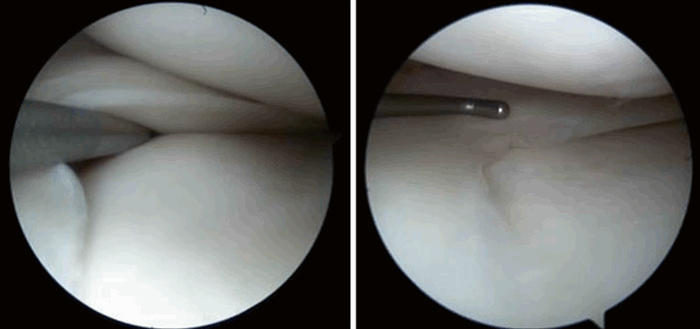

Рис. 5. Артроскопическая картина повреждения менисков: а) Лоскутный разрыв тела мениска по типу “собачьего уха”; б) Разрыв-расслоение мениска.

Чаще всего это эндоскопическое вмешательство, выполняемое через небольшие проколы. Во время операции артроскопии, выполняемой в условиях операционной, под обезболиванием, с использованием современного оборудования, в полость сустав помещается эндоскоп диаметром 4,5 мм.

На первом этапе операции врач обследует полость сустава, оценивает состояние структур. При выявлении повреждения мениска (медиального, латерального), учитывая анамнез, клинику, предварительно информируя пациента (во время беседы перед операцией) может быть выполнена резекция (удаление) поврежденной части мениска, либо его шов (в случае массивного травматического разрыва в красной зоне).